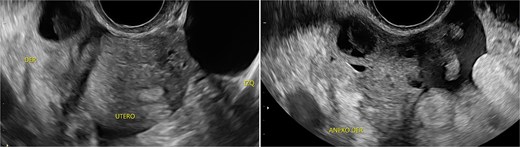

Stage III pelvic inflammatory disease (PID) was suspected based on ultrasound (Figs 1–3) and gynecological examination, which revealed mild bulging of the right lateral fornix, cervical motion tenderness, and a white, non-foul-smelling vaginal discharge. Empiric intravenous antibiotic therapy was initiated, followed by exploratory laparotomy via a Pfannenstiel incision. Intraoperative findings included an 8 × 5 cm uterus, edematous fallopian tubes, and a simple 5 × 5 cm left adnexal cyst. Cystectomy was performed.

Transverse transvaginal ultrasound demonstrating a 4.7 cm bilocular cyst in the left ovary and a dominant follicle in the right ovary, with moderate periovarian fluid adjacent to the right ovary.

Transpelvic ultrasound reveals a heterogeneous mass adjacent to the right adnexa measuring 4.6 × 8.4 cm, predominantly hypoechoic with anechoic areas.

The cervical motion tenderness—a minimum diagnostic criterion—along with fever and elevated CRP, led to a misdiagnosis of PID, with the ultrasound mass interpreted as a tubo-ovarian complex. Retrospectively, both low-normal hemoglobin and absence of mucopurulent cervical discharge were notable. When mucopurulent discharge and leukocytes on vaginal wet prep are absent, PID is unlikely, and alternative diagnoses should be considered [6].

IMTs lack distinctive imaging characteristics. Ultrasound often shows increased vascularity. Contrast-enhanced computed tomography is the imaging modality of choice for gastrointestinal IMTs, which typically present as hypodense, heterogeneous, well-defined masses frequently mistaken for colorectal carcinoma [7].